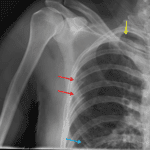

- No acute fracture or malalignment involving the shoulder

- Acute mildly displaced fractures of the right lateral fifth and sixth ribs and of the right anterior fourth rib

- Small right apical pneumothorax

- Partially imaged cervical spine fusion hardware

No acute fracture or malalignment involving the shoulder.

Acute mildly displaced fractures of the right lateral fifth and sixth ribs and of the anterior right fourth rib with a small right apical pneumothorax.

Joint spaces are maintained.